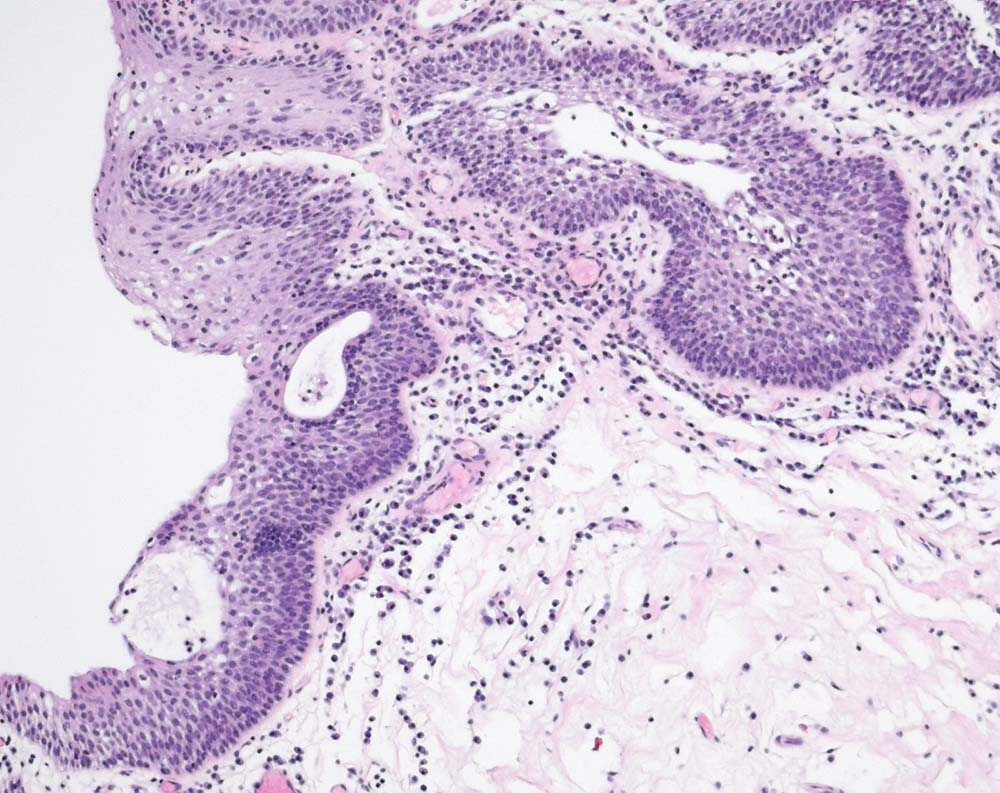

PathoPic – image database / PathoPic ID 9180 - Plattenepithelmetaplasie der Harnblasenschleimhaut

Plattenepithelmetaplasie der Harnblasenschleimhaut

Metaplasie / Heterotopie

Harnblase

Niere, Harnwege

Histologie

100